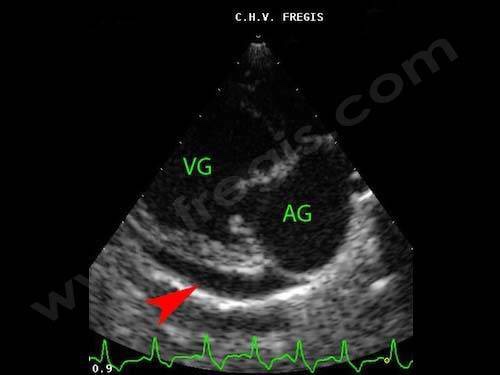

È caratterizzata da ampio e lento versamento pericardico, con conseguente accumulo di liquido. Ecocardiograma De Um Paciente Com Pericardite Constritiva Setas Rv Download Scientific Diagram Source: www.researchgate.net